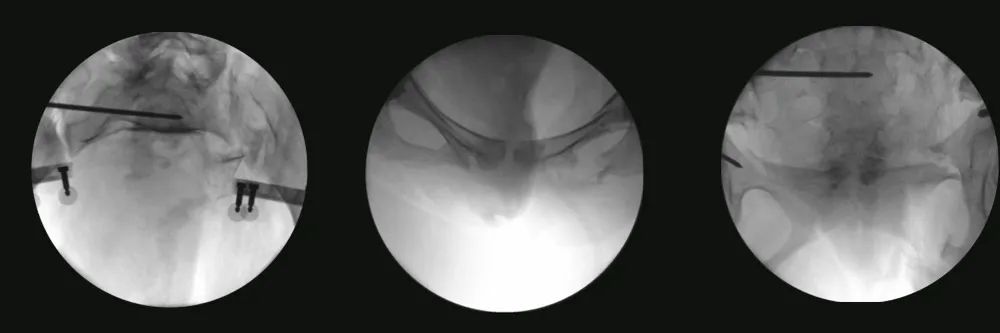

随后,术者分别将手术机械臂和机器人机械臂与患者健侧、患侧稳定固定、把持,并使用?弹性电动骨科牵引架与患者下肢稳定连接。通过对复位位置及路径进行预览并确认复位规划后,使用智能化骨科手术机器人特有的力-位协同控制模式,在全程多角度实时可视、监控下,自动完成骨盆骨折闭合复位,术中透视验证复位结果令人满意。

图五:术中透视验证复位结果